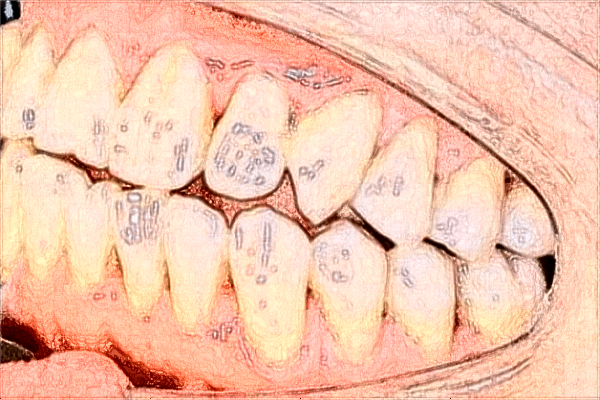

青島市立醫(yī)院牙齒正畸案例

在上學的時候我的牙齒就不是特別漂亮,有一些齙牙的狀態(tài),看上去不是特別美觀,這樣的牙齒伴隨了我20年左右的時間,自從大學畢業(yè)之后就開始關(guān)注牙齒正畸,想要通過牙齒正畸的方法來,可是又不知道該去哪一家醫(yī)院,從網(wǎng)上查閱了很多醫(yī)院的資料,經(jīng)過再三的對比,終來到青島市立醫(yī)院,之所以選擇這家醫(yī)院,主要就是因為他們有這樣的實力,而且做牙齒正畸的技術(shù)很不錯,來到這所醫(yī)院之后果然沒有讓我失望,醫(yī)生的態(tài)度特別好,根據(jù)我的實際情況給我做了牙齒正畸,戴上牙套的時候有很多不適感,不過大約一星期左右的時間慢慢的就適應了,如今已經(jīng)過去一年半了,我的牙齒也變得特別整齊,不得不說青島市立醫(yī)院牙齒正畸的技術(shù)真的是很不錯。